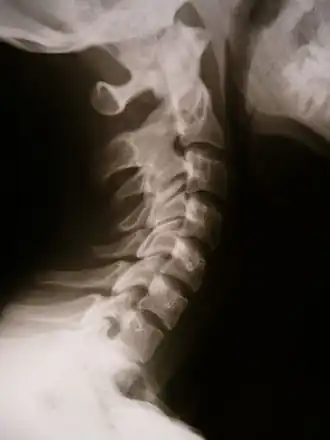

X-ray showing synostosis in the cervical spine

Synostosis (from Ancient Greek συν- (syn-) 'together' and ὀστέον (ostéon) 'bone'; plural: synostoses) is fusion of two or more bones. It can be normal in puberty (e.g. fusion of the epiphyseal plate to become the epiphyseal line), or abnormal. When synostosis is abnormal it is a type of dysostosis. Examples of synostoses include: